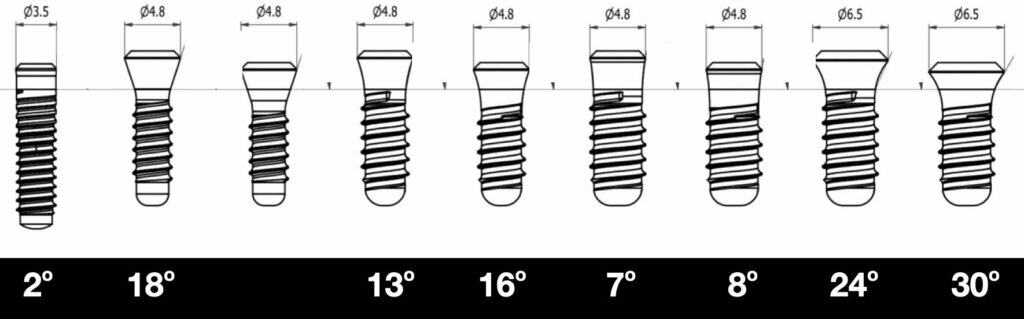

Not by default, but there could be an indirect advantage. If we accept that the deep angle matters, Tissue Level implants do exactly this: they “lock” the deep angle within a certain array of options. This will limit our ability to individualise the design, but at the same time it will prevent anyone from overcontouring straight from the level of bone. Looking at the geometry of the Tissue Level implants, one can see directly that they do not have just one angle in the collar. Instead, there can be different angles from 2o to 28o depending on the implant type and dimensions. The good news however is that it never goes beyond 30o. In particular the good old original Standard Tissue Level would ensure at all times a height of 2.8 mm with a fixed deep angle of only 13o ! You can see it as a built-in, fool-proof protection mechanism against bad design: no matter how you try, you just can’t mess it. The collar of the implant will always “lock” the first 3 mm of your supracrestal complex into a biologically acceptable configuration. Interestingly, the new TLX collar design extends this to also a convex profile, which might add more to the benefit of the collar. I do not know of the actual angles of the TLX, but they appear similar to me.

Tissue level implants are not the same in terms of deep angle, even within the same brand (Straumann S, SP in the picture above). Depending on diametre and height of collar, angle changes but is never wider than 30o.